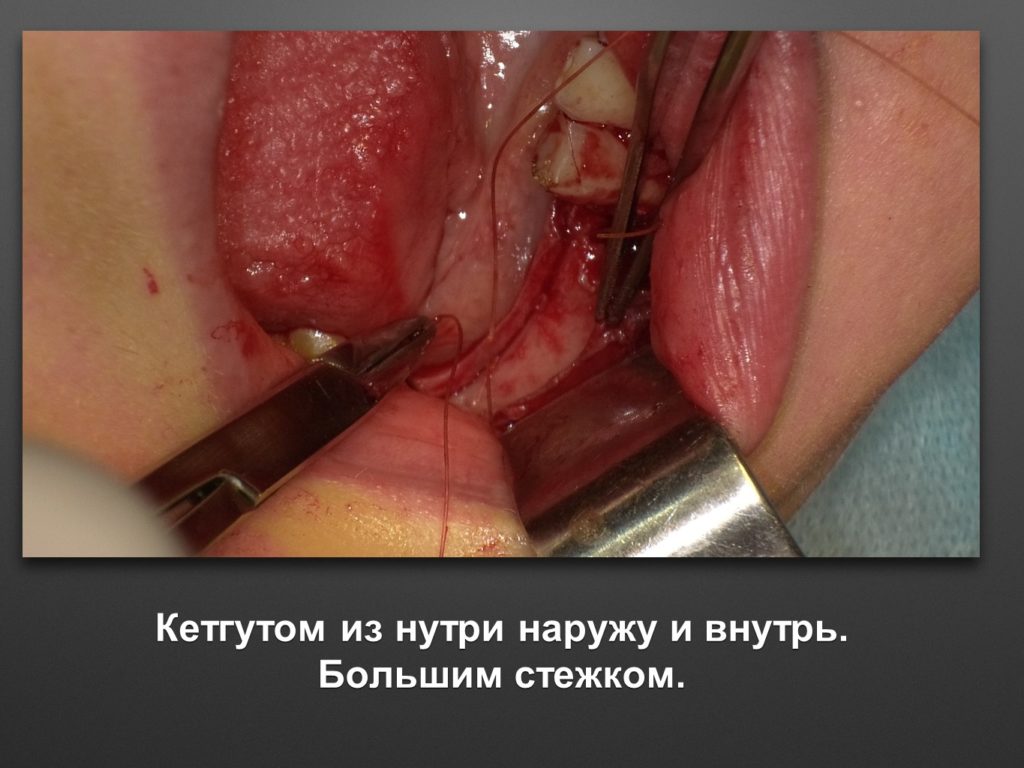

КУПИТЬ ИГЛОДЕРЖАТЕЛЬ KOHLER 4068

КУПИТЬ ИГЛОДЕРЖАТЕЛЬ KOHLER 4068

КУПИТЬ ИГЛОДЕРЖАТЕЛЬ KOHLER 4068

КУПИТЬ ИГЛОДЕРЖАТЕЛЬ KOHLER 4068